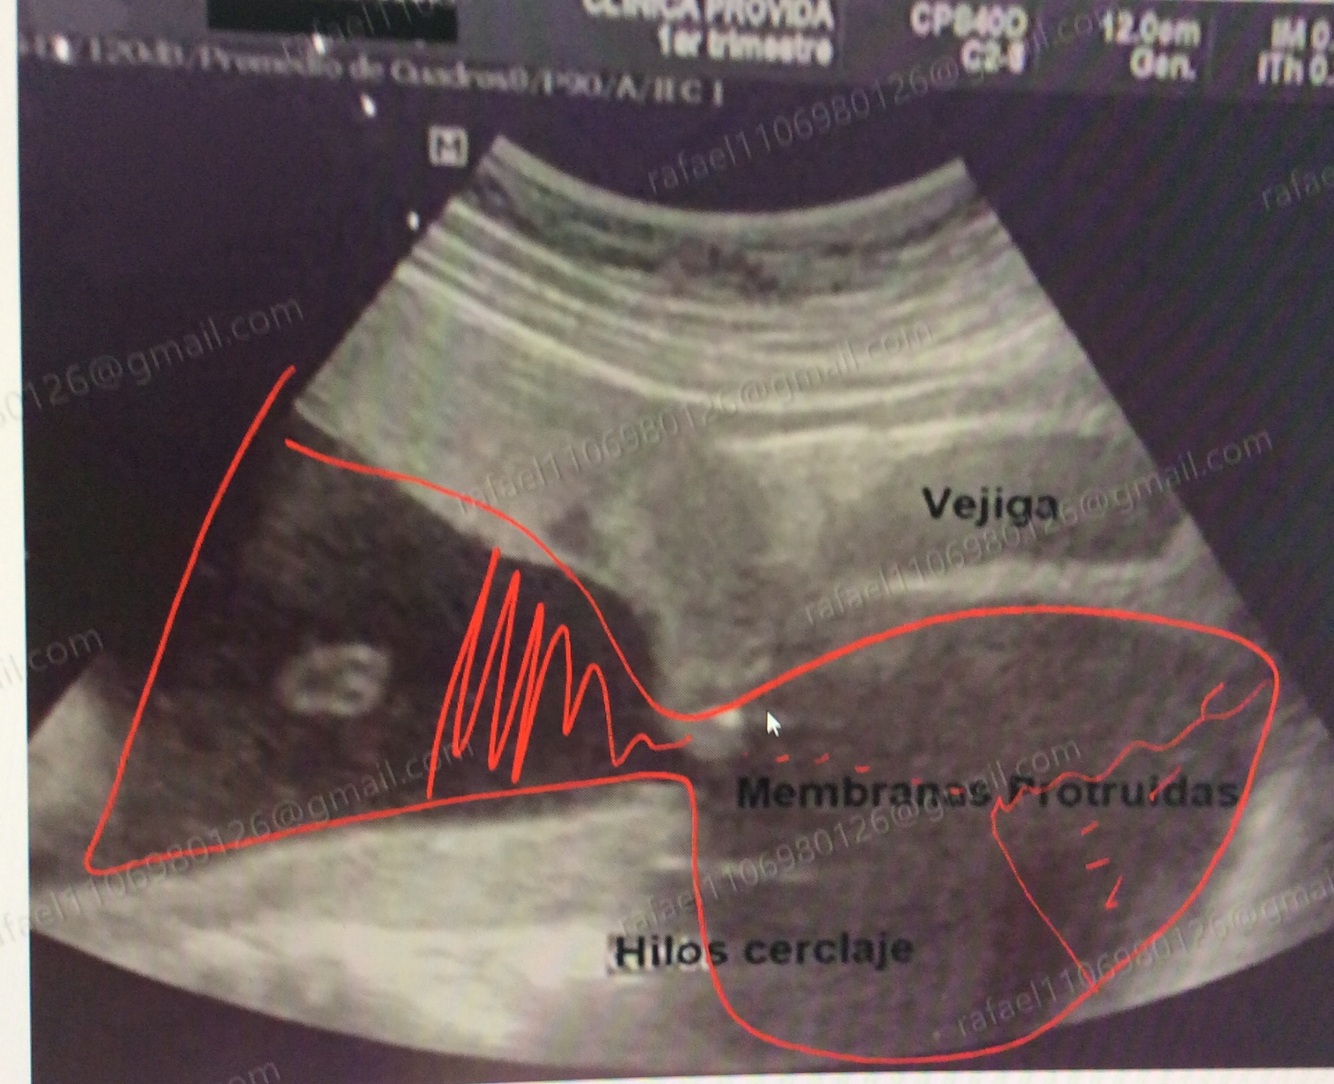

¿ Cómo se le conoce a este hallazgo ultrasonográfico ?

Imagen en reloj de arena ( membranas y líquido en vagina )

Características de incompetencia cervical

Clinica

• Membranas integras y por fuera del cervix que incluso llega a la vagina ( imagen en reloj de arena )